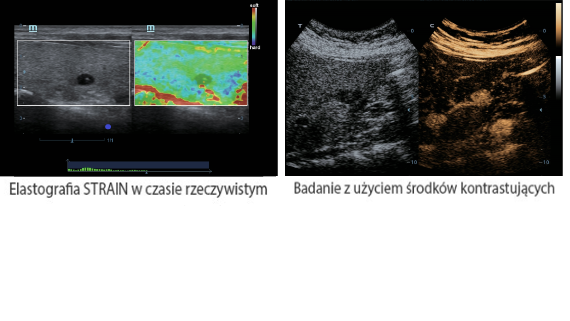

X-Insight to rozwi?zanie umo?liwiaj?ce wnikliw? analiz?, zapewniaj?c bardziej szczeg├│?owy obraz.

Opieraj?c si? na analizie potrzeb klienta, DC-60 Exp X-Insight zosta? zaprojektowany tak, aby znacznie usprawni? diagnostyk?, kt├│ra jest wspomagana przez technologi? eXpress Clarity, eXceptional Intelligence i eXceeding Experience.

Obrazy kliniczne